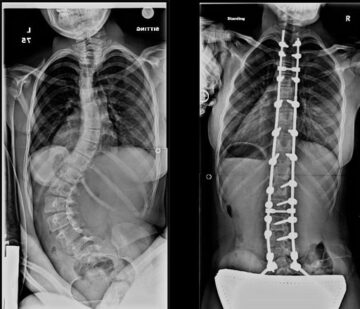

أبريل 28, 2026 هل تحسّن جراحة اعوجاج العمود الفقري العصبي العضلي جودة الحياة؟ وما النتائج المتوقعة ع… scoliosis, اعوجاج العمود الفقري, الجنف لا يوجد تعليق 5 المشاهدات هل تحسّن جراحة اعوجاج العمود الفقري العصبي العضلي جودة الحياة؟ وما النتائج المتوقعة عند الأطفال؟ مقدمة: سؤال مهم يشغل كل أسرة عندما يُشخَّص الطفل بحالة اعوجاج العمود الفقري المرتبط بأمراض عصبية عضلية، يبدأ الأهل